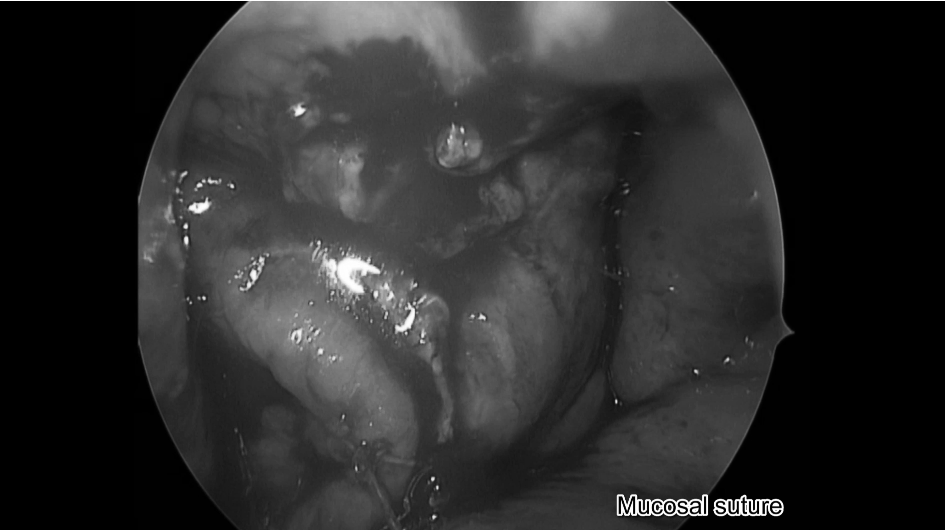

鼻腔内粘膜缝合

▼完成鼻腔内缝合,手术顺利结束

▼鼻腔内缝合示意图